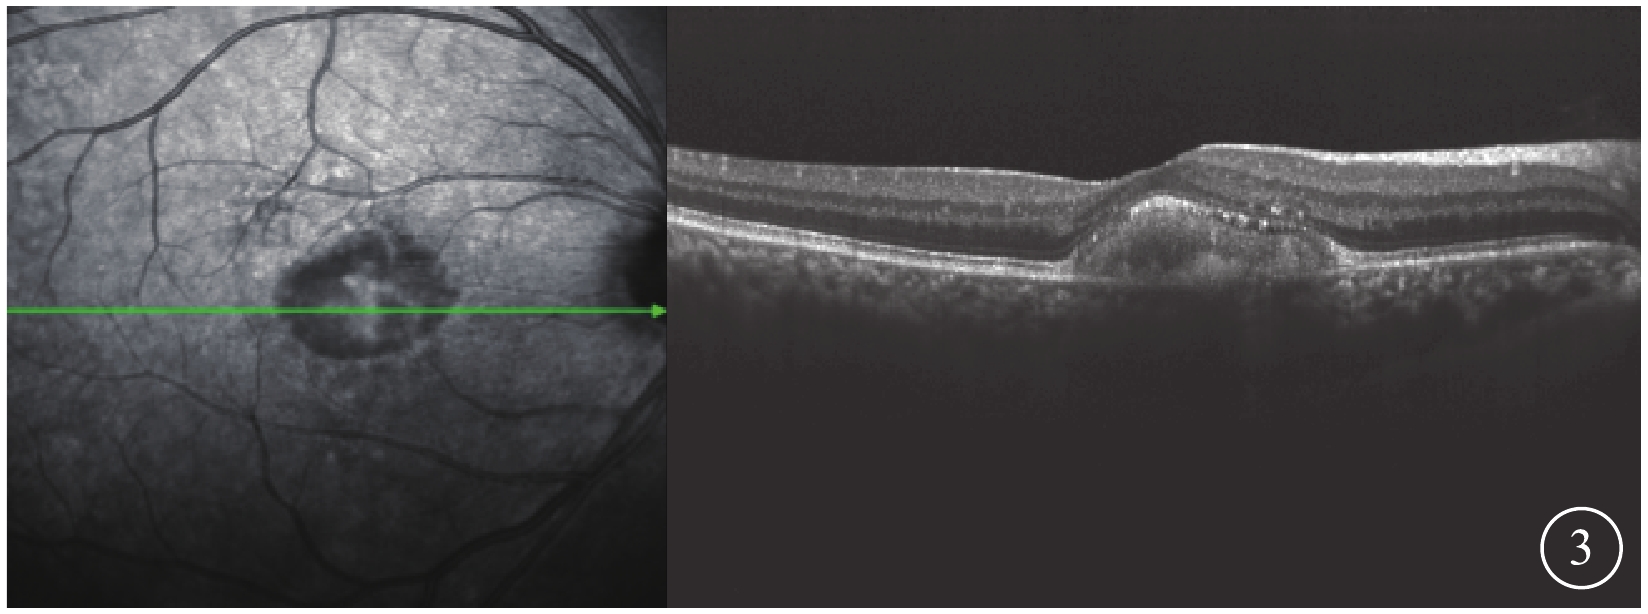

OCT檢查發現,所有患眼黃斑中心凹視網膜色素上皮(RPE)層之上可見“圓頂屋”樣隆起病灶。病灶局部的RPE層增厚,密度不均;視網膜神經上皮層除被病灶抬高外,未見明顯破裂分層現象(圖3),層間也無水腫、滲出改變。

圖3

AOFVD患眼OCT像。黃斑中心凹RPE層之上“圓頂屋”樣隆起病灶,視網膜神經上層除被病灶抬高外,未見明顯破裂分層現象

圖3

AOFVD患眼OCT像。黃斑中心凹RPE層之上“圓頂屋”樣隆起病灶,視網膜神經上層除被病灶抬高外,未見明顯破裂分層現象

OCT檢查發現,所有患眼黃斑中心凹視網膜色素上皮(RPE)層之上可見“圓頂屋”樣隆起病灶。病灶局部的RPE層增厚,密度不均;視網膜神經上皮層除被病灶抬高外,未見明顯破裂分層現象(圖3),層間也無水腫、滲出改變。

圖3

AOFVD患眼OCT像。黃斑中心凹RPE層之上“圓頂屋”樣隆起病灶,視網膜神經上層除被病灶抬高外,未見明顯破裂分層現象

圖3

AOFVD患眼OCT像。黃斑中心凹RPE層之上“圓頂屋”樣隆起病灶,視網膜神經上層除被病灶抬高外,未見明顯破裂分層現象